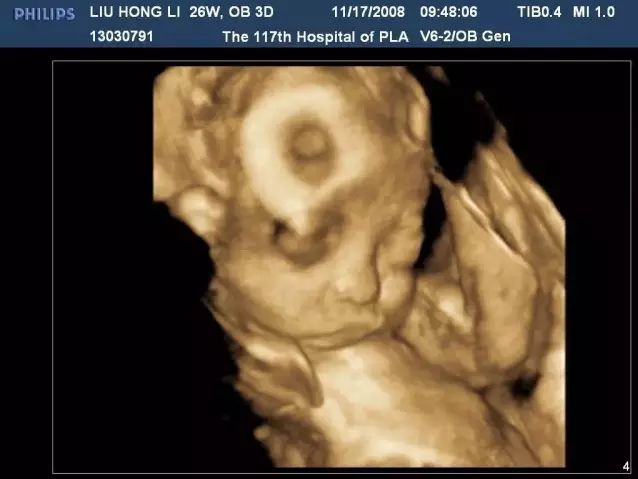

四維彩超,隔空約會(huì)小金人

這就是四維彩超帶來(lái)的魅力,讓你們可以和寶寶穿越時(shí)空提前“相見(jiàn)”

3.胎兒宮內(nèi)視頻:以動(dòng)態(tài)視頻的方式觀察胎兒在宮內(nèi)的情況,更具有連貫性,能更清晰、準(zhǔn)確的進(jìn)行記錄和排畸。

胎兒在孕20周以后,肢體以及重要臟器已經(jīng)全部發(fā)育,但在孕22~26周因胎兒器官發(fā)育更加完善,而且羊水量較多,適合做胎兒畸形篩查。